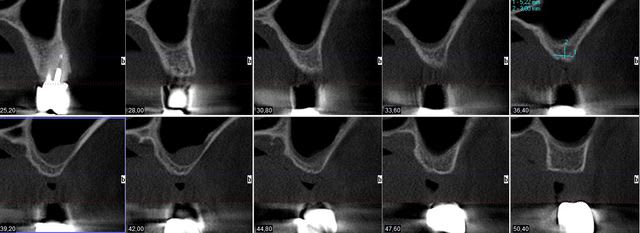

pour illustrer cette utilisation du bioactys, voici un cas (ce matin, mise en focntion des implants à 7 mois post_op)

Coupes 7mois xm3rpt - Eugenol